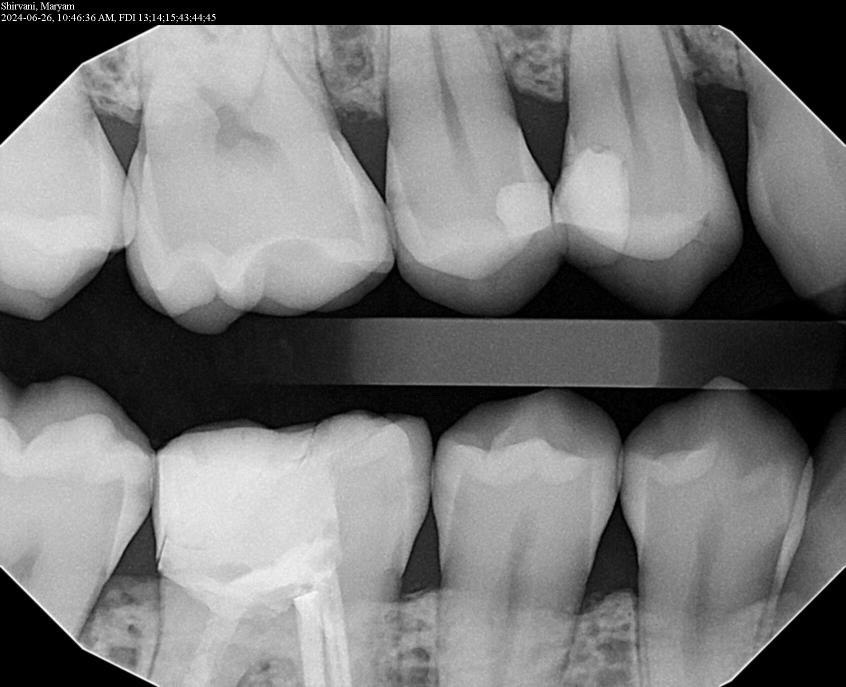

3. What surface require restoration?